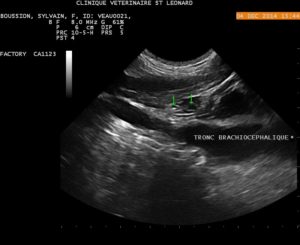

Il a ensuite réalisé un bloc échoguidé du plexus brachial, en utilisant une sonde sectorielle micoconvexe et une aiguille spinale.

Le positionnement de la sonde dans le creux axillaire et l’introduction de l’aiguille dans une direction cranio-caudale sont montrés ici :

Avant injection, les flèches vertes montrent les nerfs du plexus brachial, sous le muscle pectoral, en coupe transversal.